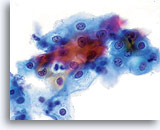

En raison de leur morphologie, les cellules issues de lésions de bas grade comptent parmi les anomalies intra-épithéliales les plus faciles à localiser et à identifier. En comparaison, les noyaux LSIL sont les plus grands et présentent un rapport N/C inférieur aux HSIL ou carcinomes. Ces cellules affichent une atypie nucléaire plus importante que les ASCUS (ce qui se traduit par une augmentation de la taille nucléaire, une irrégularité de la chromatine et une irrégularité de l’enveloppe nucléaire). Les noyaux peuvent occasionnellement ne pas être aussi hyperchromatiques que sur les frottis conventionnels, mais ils le sont toujours par rapport aux cellules normales environnantes. Les changements associés au HPV (par exemple, formation de cavités dans le cytoplasme) sont plus évidents grâce à la fixation liquide et à la technique de transfert, ce qui élimine la déformation des cellules associée à la méthode d’étalement conventionnelle. La méthode ThinPrep préserve mieux ces changements cellulaires, ce qui permet une meilleure distinction entre les véritables cavités cytoplasmiques induites par le HPV et les vacuoles bénignes/dégénératives et/ou les cellules malpighiennes glycogénées.

Comme il s’agit de cellules malpighiennes matures, elles gardent leur forme polygonale et conservent en partie leur taille normale. La taille des noyaux est au moins 3 à 4 fois supérieure à celle d’une cellule intermédiaire normale. En revanche, quand les changements associés au HPV sont évidents, les cellules peuvent être plus petites (quasiment parakératosiques), tout comme les noyaux (quelque peu pycnotiques) qui présentent en outre une binucléation et/ou multinucléation. Ces noyaux pycnotiques affichent en outre des caractéristiques anormales : hyperchromasie, augmentation de la taille par rapport à une cellule malpighienne superficielle normale, légère variation de la forme et de la taille, etc. Il est important d’insister sur le fait qu’une interprétation de LSIL/HPV implique des cavités cytoplasmiques nettes accompagnées de la morphologie nucléaire anormale décrite ci-dessus.

Dans certains cas, on trouve un mélange de cellules LSIL et HSIL, et l’anomalie la plus grave doit être interprétée en priorité sur la lame ThinPrep. Il s’avère parfois difficile de faire la distinction entre les LSIL et les HSIL. Les critères en faveur des HSIL incluent un rapport N/C élevé, un cytoplasme immature et un nombre plus important d’anomalies nucléaires. En raison du manque de cellules anormales ou de critères véritablement intermédiaires, les cas rares de SIL ne peuvent pas être placés dans une catégorie. Comme ces cas vont probablement progresser, il semble plus prudent d’utiliser un terme tel que “SIL, grade impossible à déterminer”. Même si la plupart des études de suivi des LSIL TP font le plus souvent apparaître des changements de bas grade associés à la biopsie, environ 15 à 20 % des cas de LSIL sont suivis de biopsies de haut grade.